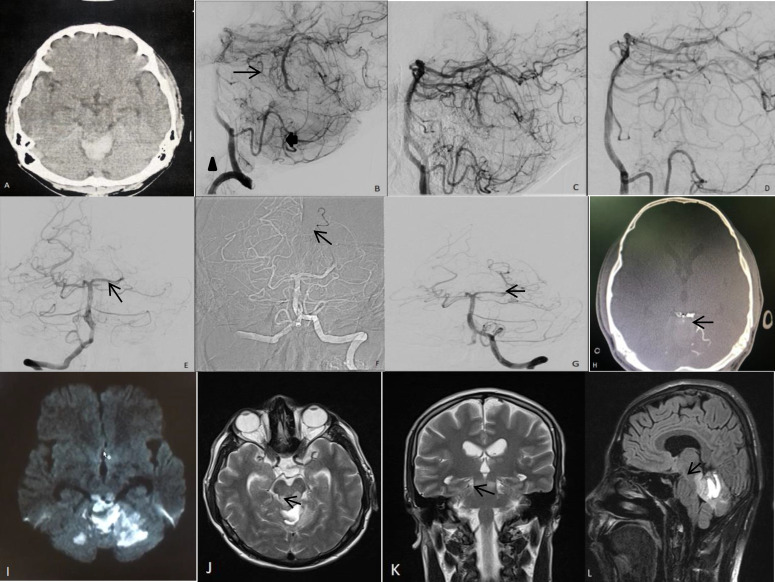

Tinnitus and reduced word recognition with a bilateral inferior colliculus infarction after cerebellar arteriovenous malformation embolization.